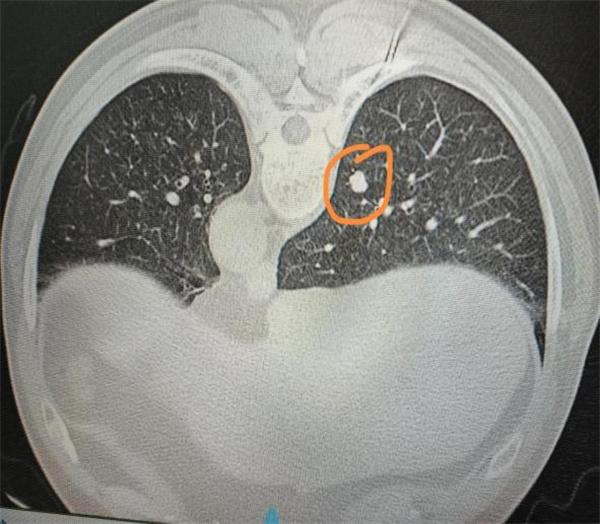

患者雷先生因体检发现左下肺结节前来就诊,该结节大小仅7mm,位于左肺内且距离胸膜约7cm,不仅位置深,还存在边缘不规整、似有分叶等特征,临床高度怀疑恶性可能。这一诊断结果让雷先生及家属陷入极大焦虑,担心结节恶变的阴影使其寝食难安,正常生活受到严重影响。

术前,团队依托CT影像技术,对病灶的大小、位置、深度及与周边肺组织、胸膜腔的关系进行反复精准测量与评估,从穿刺肋间选择、进针角度调整到路径规划,每一个环节都经过严谨论证。